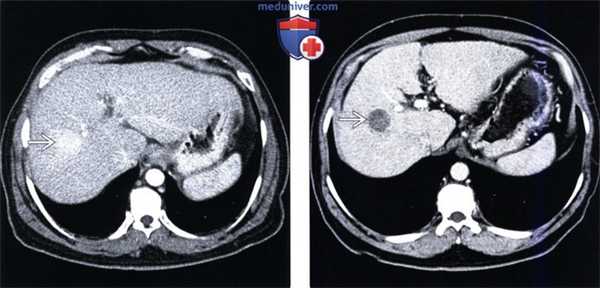

(Слева) На КТ в артериальной фазе контрастного усиления в правой доле печени определяется невыраженный гиперваскулярный узел размером около 2 см (гепатоцеллюлярный рак) наряду с признаками цирроза: расширением фиссур и т.д.

(Справа) На КТ в портально-венозной фазе контрастного усиления у этого же пациента определяется «вымывание» контраста из опухоли, типичное для гепато-целлюлярного рака. Лечение осуществлялось путем трансартериальной химиоэмболизации, в т. ч. с введением липиодола.

(Слева) На контрольной КТ без контрастного усиления у этого же пациента определяется накопление липиодола, содержащего йод, в опухоли. Обратите внимание на косвенные признаки повреждения печени: уменьшение объема правой доли и асцит.

(Справа) На КТ в артериальной фазе контрастного усиления определяется повышение плотности части латерального сегмента печени (ПРПП) и раннее заполнение контрастом ветвей воротной вены, подходящих к этому сегменту. Эти изменения обусловлены артерио-портальным шунтом и, вероятно, являются результатом ранее выполненной биопсии печени в этой области.